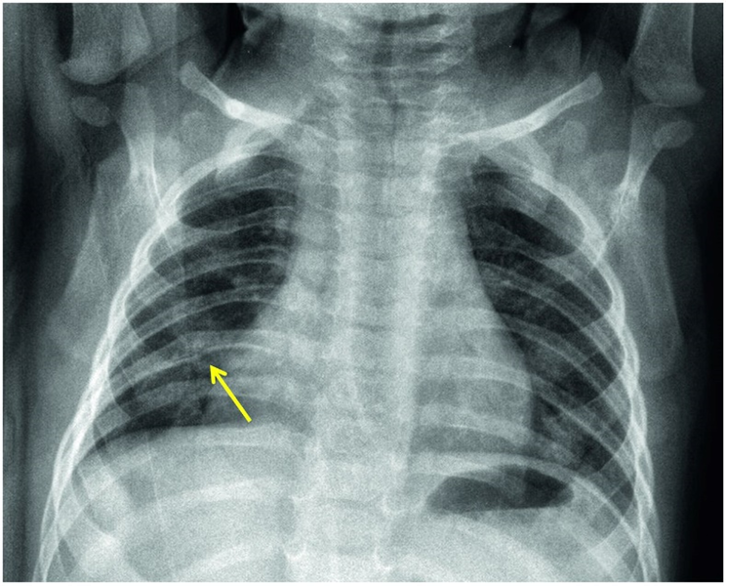

The diagnosis of bronchiolitis is clinical (based on the patient’s history and physical examination). Laboratory testing and radiographic studies are not recommended for diagnosis. CBC, inflammatory markers, blood culture, and chest x-ray should only be used when a serious bacterial infection (SBI) is suspected. A viral respiratory panel may be used to aid in the more accurate diagnosis of the viral pathogen, which may be useful for the hospitalized patient or in patients not following the expected course of illness. A chest x-ray may be performed to rule out conditions like effusions or pneumothorax when there is clinical suspicion but should not be used to evaluate for pneumonia as that is a clinical diagnosis. In bronchiolitis, the chest x-ray may show hyperinflation of the lungs, atelectasis, or peribronchial cuffing that is often referred to as the classic cheerio (see CXR).